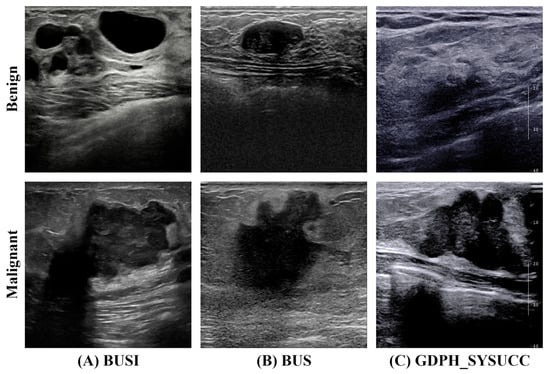

Robust Dual-Stream Diagnosis Network for Ultrasound Breast Tumor Classification with Cross-Domain Segmentation Priors

Ultrasound imaging is widely used for early breast cancer screening to enhance patient survival. However, interpreting these images is inherently challenging due to speckle noise, low lesion-to-tissue contrast, and highly variable tumor morphology within complex anatomical structures. Additionally, variations in image characteristics across institutions and devices further impede the development of robust and generalizable computer-aided diagnostic systems. To alleviate these issues, this paper presents a cross-domain segmentation prior guided classification strategy for robust breast tumor diagnosis in ultrasound imaging, implemented through a novel Dual-Stream Diagnosis Network (DSDNet). DSDNet adopts a decoupled dual-stream architecture, where a frozen segmentation branch supplies spatial priors to guide the classification backbone. This design enables stable and accurate performance across diverse imaging conditions and clinical settings. To realize the proposed DSDNet framework, three novel modules are created. The Dual-Stream Mask Attention (DSMA) module enhances lesion priors by jointly modeling foreground and background cues. The Segmentation Prior Guidance Fusion (SPGF) module integrates multi-scale priors into the classification backbone using cross-domain spatial cues, improving tumor morphology representation. The Mamba-Inspired Linear Transformer (MILT) block, built upon the Mamba-Inspired Linear Attention (MILA) mechanism, serves as an efficient attention-based feature extractor. On the BUSI, BUS, and GDPH_SYSUCC datasets, DSDNet achieves ACC values of 0.878, 0.836, and 0.882, and Recall scores of 0.866, 0.789, and 0.878, respectively. These results highlight the effectiveness and strong classification performance of our method in ultrasound breast cancer diagnosis. Full article

Figure 1